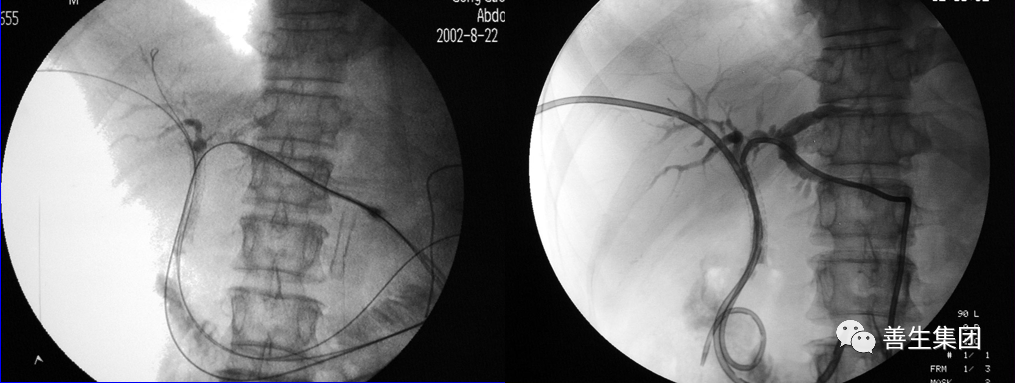

皮肤巩膜黄染伴皮肤瘙痒20余日,胰头MT。

MIR和CT

PTC造影+MIR胆道

双导丝+左右肝管分别引流

PTCD